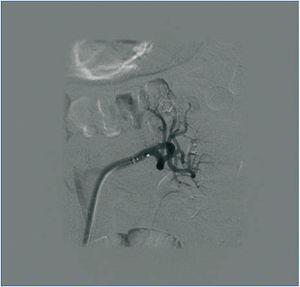

Hasta que se decidió la realización de DNSR, el paciente precisó 10 ingresos hospitalarios por situación de urgencia hipertensiva, en los que se recomprobó la resistencia al tratamiento. Ante la imposibilidad de obtener el control de su PA, y tras descartar posibles contraindicaciones para su empleo2,3 (figura 1), en enero de 2012 se procedió a la aplicación del procedimiento endovascular de DNSR, vía femoral, previa monitorización y premedicación, según la técnica recomendada. En ese momento, el paciente presentaba una HTA grado 3, con signos de lesión en órgano diana (LOD): hipertrofia ventricular izquierda (HVI), retinopatía hipertensiva grado 2, microalbuminuria, y recibía tratamiento con: telmisartán/amlodipino 80/10 mg: 1/12 horas, aliskiren 300 mg: 1/24 horas, eplerenona 50 mg: 1/12 horas, doxazosina 8 mg: 1/8 horas, hidroclorotiazida 25 mg: 1/24 horas, carvedilol 25 mg: 1/12 horas.

Figura 1. Angio-TAC antes de la DNSR. Presencia de polar inferior en riñón izquierdo